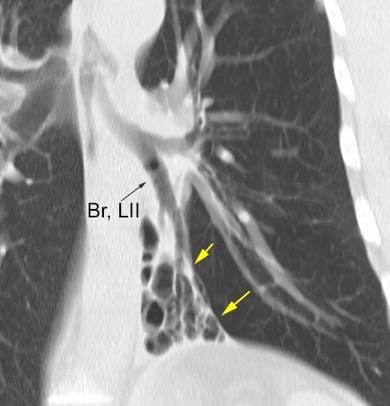

WINDEMERE” . SÍNDROME DE LADY

Forma indolente. Supresión de la tos. Língula y LM los más frecuentemente afectados. Bronquiectasias.

Coexistencia con nódulos centrilobulillares y patrón en mosaico muy sugerente.

Micobacteria atípica

Frecuencia en “clusters” familiares. Factores genéticos de sensibilidad del huésped a la infección pulmonar.

Colombo RE et al. Familial Clustering of Pulmonary Nontuberculous Mycobacterial Disease. Chest 2010./ Olivier KN. Lady Windermere Dissected: More Form Than Fastidious. Ann Am Thorac Soc. 2016/Martínez S et al. The many faces of pulmonary Nontuberculous Mycobacterial infection. AJR. 2007